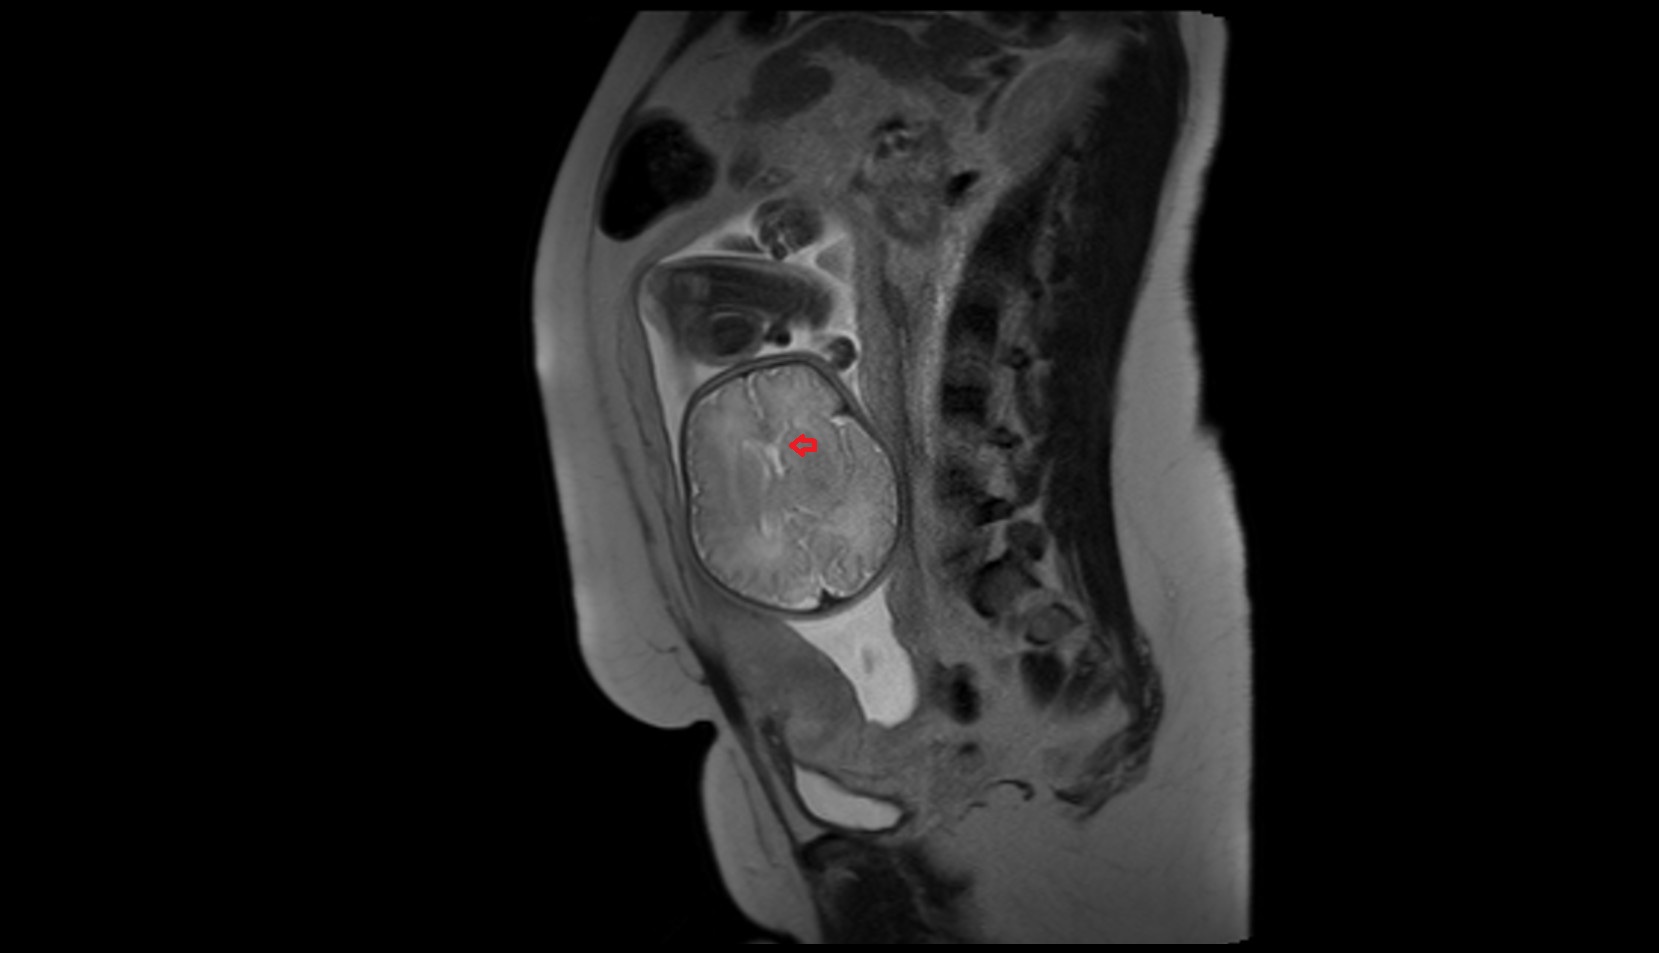

- Placenta

- Uterus (pregnancy)

- Amniotic fluid

- Umbilical cord

- Urinary Bladder in Pregnancy

- Cervix in Pregnancy

- Vagina in Pregnancy

- Fundus of uterus in pregnancy

- Fetal brain

- Fetal caudate nucleus

- Fetal thalamus

- Fetal pons

- Fetal cerebellum